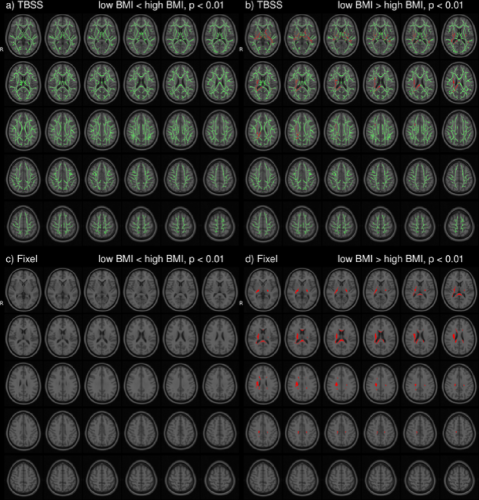

In the HCP dataset, ODFs correlate strongly with the demographic variable BMI. As expected, the ODFs negatively correlate (Fig. 7b) with BMI, indicating a loss of anisotropy with increasing BMI (Fig. 5a,b). This result is consistent with the well-established negative association between global white matter integrity and physical obesity (Mueller et al., 2011; Stanek et al., 2011; Verstynen et al., 2012; Gianaros et al., 2013; Verstynen et al., 2013). The fiber directions (Fig. 8a,b) identified from can be used to perform tractography (Fig. 8c,d). Resulting tracts (Fig. 8c,d) show a pronounced loss of anisotropy in the corticospinal tracts, the optic radiations and the right superior longitudinal fasciculus. These results are corroborated by the existing methods TBSS (Fig. 9a,b, S2a,b), Connectivity-based fixel enhancement (Fig. 9c,d, S2c,d) and local connectometry (Fig. 9e,f, S3a,b). The volume of positive findings of correlation with BMI is largest when using the full ODF information with the ODF approach (Fig. 9). In addition, in a test of specificity, no voxels are found to correlate with randomly permuted BMI (Fig. S4).

Several methods exist to analyze populations of diffusion MRI datasets, typically working on a reduced dimensionality subset of the diffusion data. TBSS (Jbabdi et al., 2010), limiting the analysis to a projection to a tract skeleton, succeeds in identifying the tracts most significantly correlated with BMI (analysis of FA, Fig. 9a,b, S2a,b) but misses the full extent of the correlations. The Connectivity-based fixel enhancement (Raffelt et al., 2015) and Connectometry (Yeh et al., 2016) approaches do include more of the available information and hence perform better than the TBSS method (Fig. 9c,d, S2c,d (Fixel enhancement) and 9e,f, S3a,b (Connectometry) vs 9a,b, S2a,b (TBSS)).

None of the above methods however capitalizes on the full ODF information. This in contrast to the approach presented in this paper. The ODF approach indeed identifies a larger volume of significant findings (227 cm3) than the existing methods tested here (TBSS 17 cm3, Connectivity-based fixel enhancement 15 cm3 and Connectometry 212 cm3, Fig. 9b,d,f,h,j). That is, by analyzing the full ODF information and not reducing the dimensionality of the diffusion data, as is commonly done, the ODF approach is able to pick up on smaller significant changes, better grasping the full extent of the significant findings. Limitations on computational power and diffusion acquisitions (e.g. DTI) which inspired the data reduction of older methods no longer exist. It is hence advisable to maximize the amount of information included in the analysis as in the approach presented here.